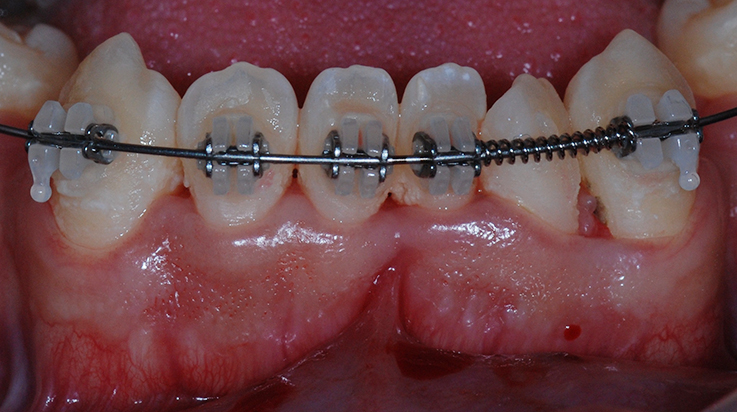

Clinical procedure increasing thickness of gingiva with soft tissue graft and collagen matrix